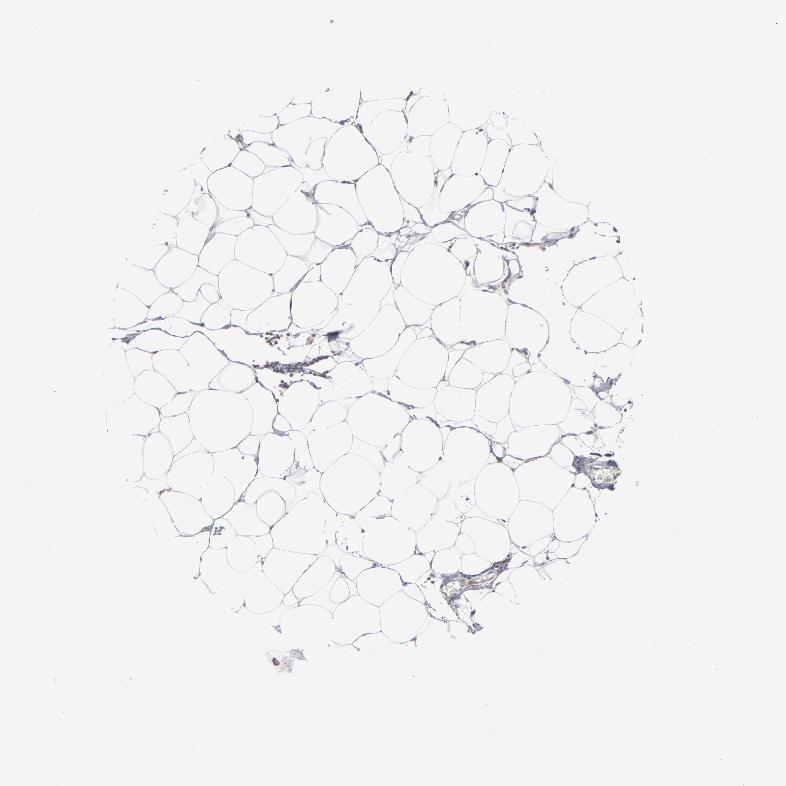

SOFT TISSUE 1 - Antibody stainingi

Antibody staining in the annotated cell types in the current human tissue is reported as not detected, low, medium, or high, based on conventional immunohistochemistry profiling in selected tissues. This score is based on the combination of the staining intensity and fraction of stained cells.

Each image is clickable and will lead to virtual microscopy that enables deeper exploration of all samples and also displays staining intensity scores, fraction scores and subcellular localization as well as patient and tissue information for each sample.

Antibody HPA002980

Fibroblasts Not detected

SOFT TISSUE 2 - Antibody stainingi

Peripheral nerve Not detected